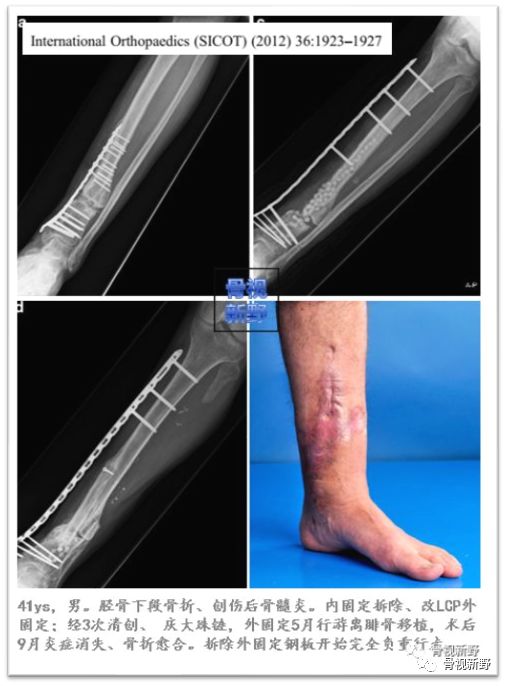

胫骨远段感染性骨不连LCP外固定

LCP外固定的其它类似报道